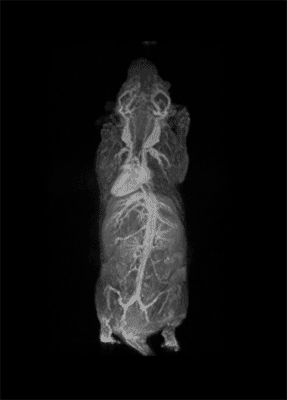

The possibility to use complementary imaging modality was our task in the last 10 or so years. And this changed quite drastically the structure of our group, because we have to get users quickly used to the basic principles in order to have efficient imaging reporter for the other imaging modalities.

So, our students now pass from one imaging modality to another to get used to the different classes of imaging reporter agents.

I think the future of molecular imaging is very bright. The possibility to look inside the body with eye spatial resolution and to look at the biochemical processes that are related to the onset of the diseases open a beautiful scenario in order to fit all the terrific achievements that have come from biology and from molecular medicine.

I think that the possibility molecular imaging is offering to look in depth inside the living system and any development in this direction that is expected for the forth coming year will make this science even more important than it is now.